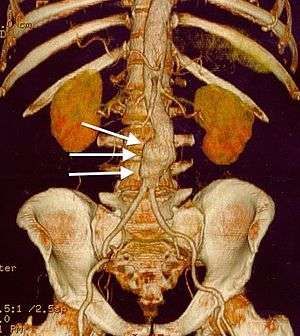

CT reconstruction image of an abdominal aortic aneurysm (white arrows) | |

Sagittal CT image of an AAA